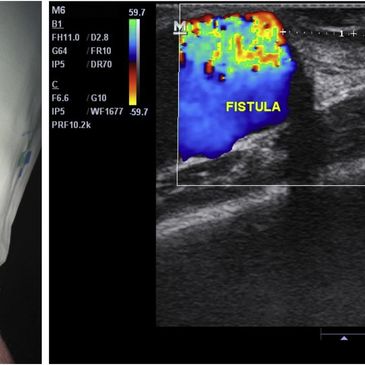

Fistula Doppler USG is non-invasive test that evaluates blood flow through an arteriovenous fistula (AVF) or graft (AVG), Its helps ensure the fistula or graft is functioning properly, optimizing dialysis treatment. The test assesses:

- Blood flow rates,

- Stenosis (Narrowing)

-Thrombosis (Clotting).